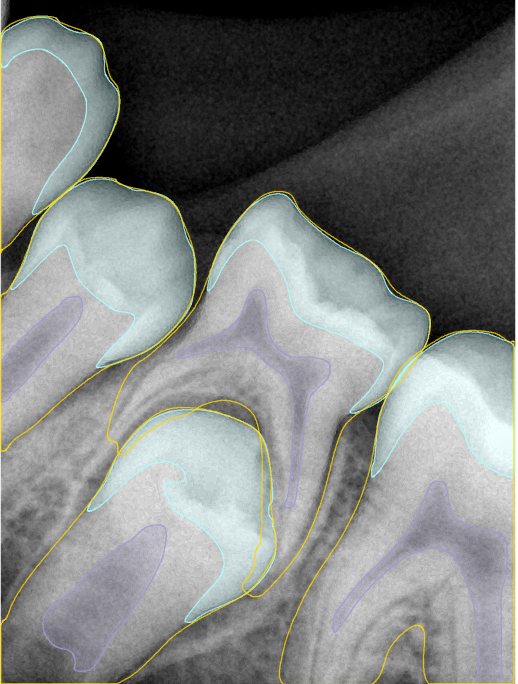

CR/DR 牙齿分割阶段记录

当前进展

- 完成了 CR/DR 牙齿相关分割训练

- 当前结果已经达到阶段预期,但仍有细节问题需要继续处理

相关测试

遇到的问题

- 训练过程中出现过 mask 下移问题

- 部分结果会出现 box 填充异常

- mask 边缘仍然有比较明显的锯齿感